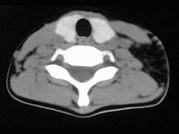

问题 女,17岁,发现左侧颈部包块半年余,PE:病灶质软,境界不清,无压痛,CT如图所示,应诊断为()

选项 A.颈部脂肪瘤 B.颈部畸胎瘤 C.颈部错构瘤 D.颈部淋巴管瘤 E.颈部陈旧性血肿

答案 A